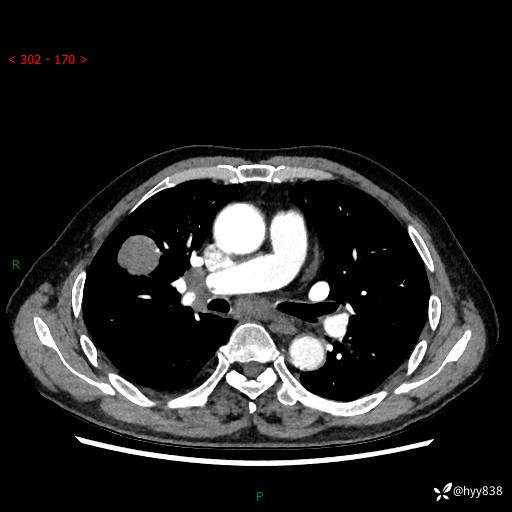

69岁/男,间断咳嗽伴气促、下肢水肿。临床拟诊肺栓,偶发肺均质强化结节--结果公布

【患者信息】:69岁/男

【主诉】:间断咳嗽伴气促、下肢水肿2周

【现病史及既往史】:患者2周来无明显诱因出现咳嗽,咳少量白痰,不易咳出,伴有气促,呈间断发作,症状与活动费力相关,以夜间为甚,不能平躺入睡,偶有憋醒,无胸闷胸痛、无发热、无头晕、头痛等不适,伴有双下肢中度水肿,就诊于当地县人民医院门诊,完善相关检查提示:左下肢深静脉血栓形成,未予以特殊处理,今患者为求进一步诊治来我院就诊,拟“心衰”收入我科。 起病以来,患者精神、饮食、睡眠可,大小便如常,体力明显下降,体重未见明显减轻。

【检查】:胸部CT增强